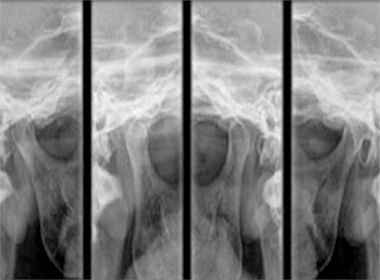

CRO/SP CL 8.832

R.T.: Marilen M. K. Kiyuna

CRO/SP 67.935